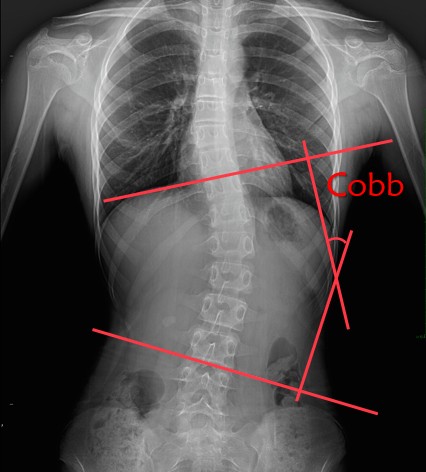

医学诊断金标准:站立位全脊柱X线片测量Cobb角,若≥10°即可确诊。

2.Cobb角:角度越大,进展风险越高。

(以Cobb角30°作为判断标准)

Cobb角<30°:骨骼成熟后基本稳定

Cobb角40°-50°:可能每年加重约1°

Cobb角>50°:心肺功能受损风险激增